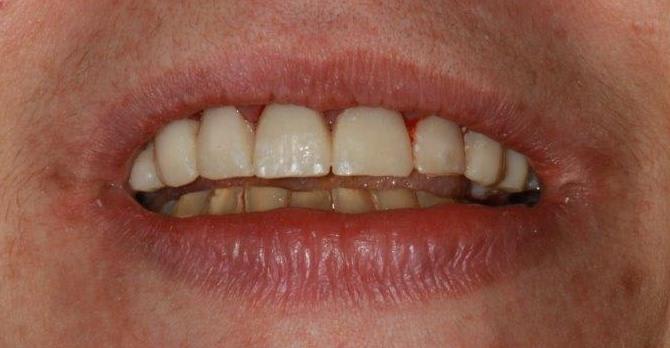

Deuxième rdv ce jour...ça prend forme, doucement

taille du haut et nouveaux provisoires

ça va me permettre de faire l point su la suite (alignement des collets etc....)